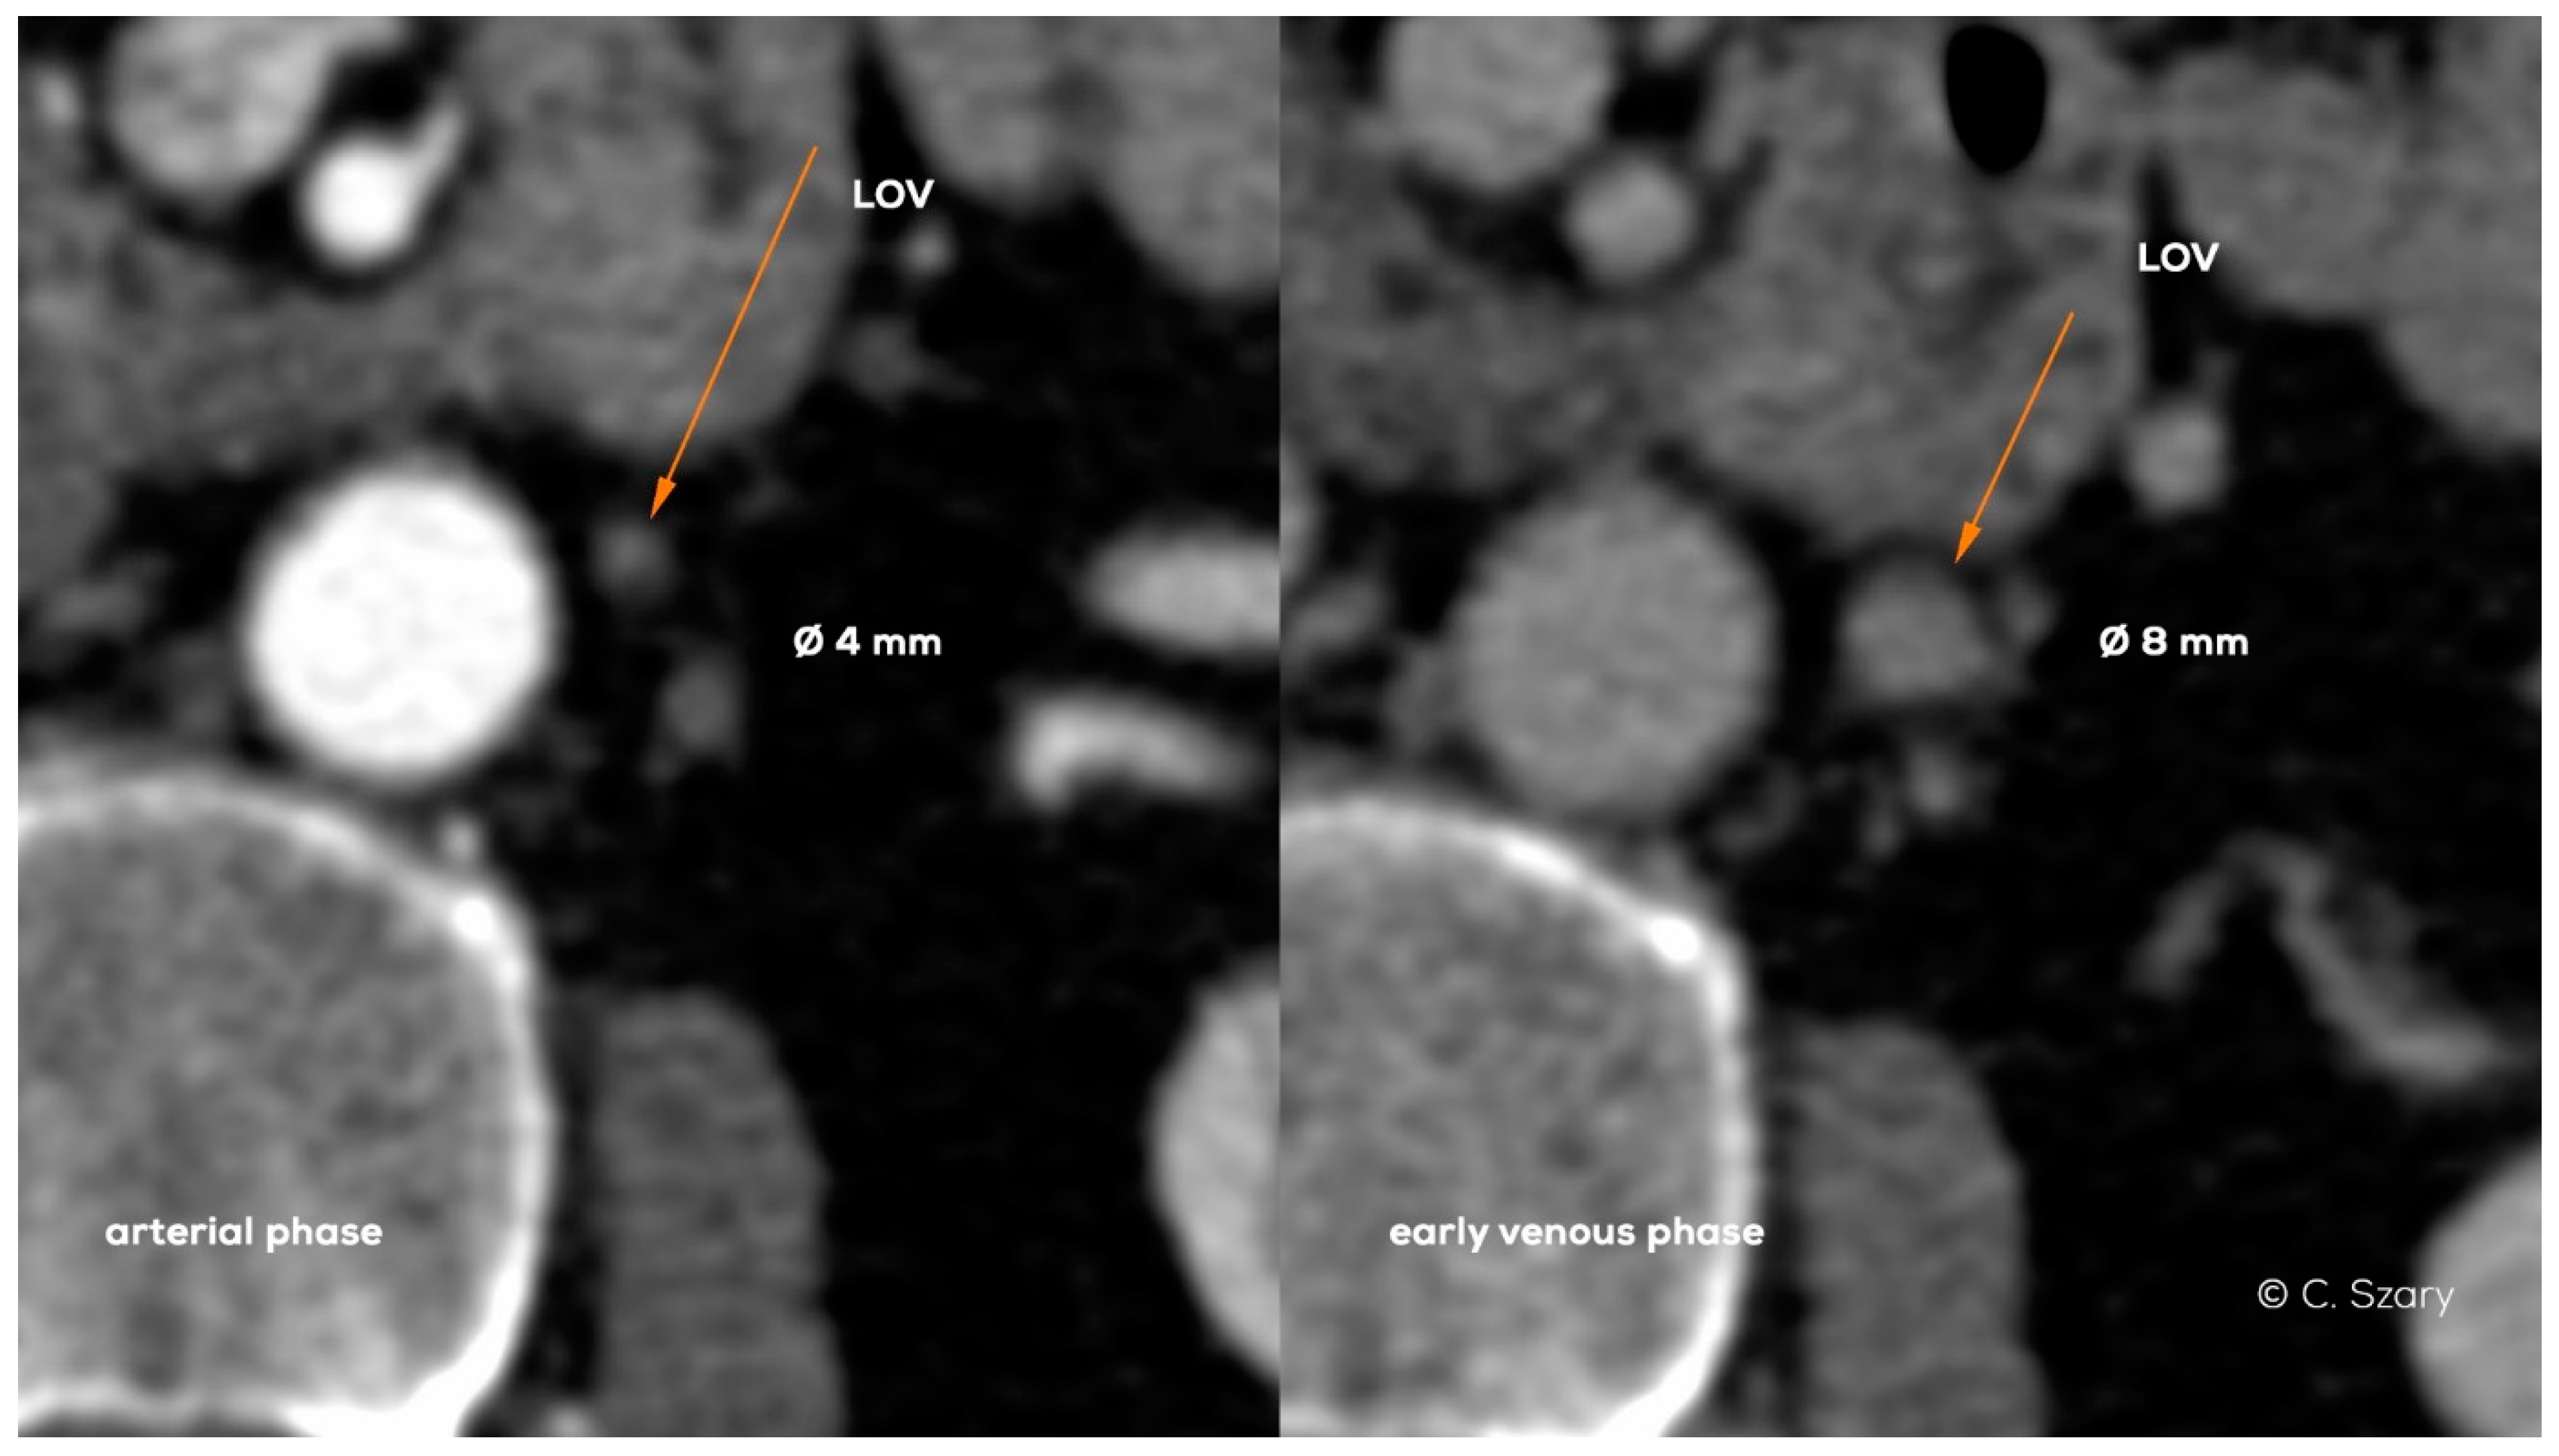

The important element for patients’ preparation is their adequate hydration, both due to the contrast agent administration and the proper filling of the vascular bed. Another equally important factor influencing the interpretation of imaging is its duration, usually several minutes for typical CTV vs. 45–50 min for MRV examination. Apart from test duration, the contrast phase and respiratory phases also significantly affect the accuracy of vein diameter measurements, which translates into the final result of evaluation (Figure 19).

Figure 19.

Axial CT images in arterial and early venous phase show significant difference in left ovarian vein (LOV) diameters.